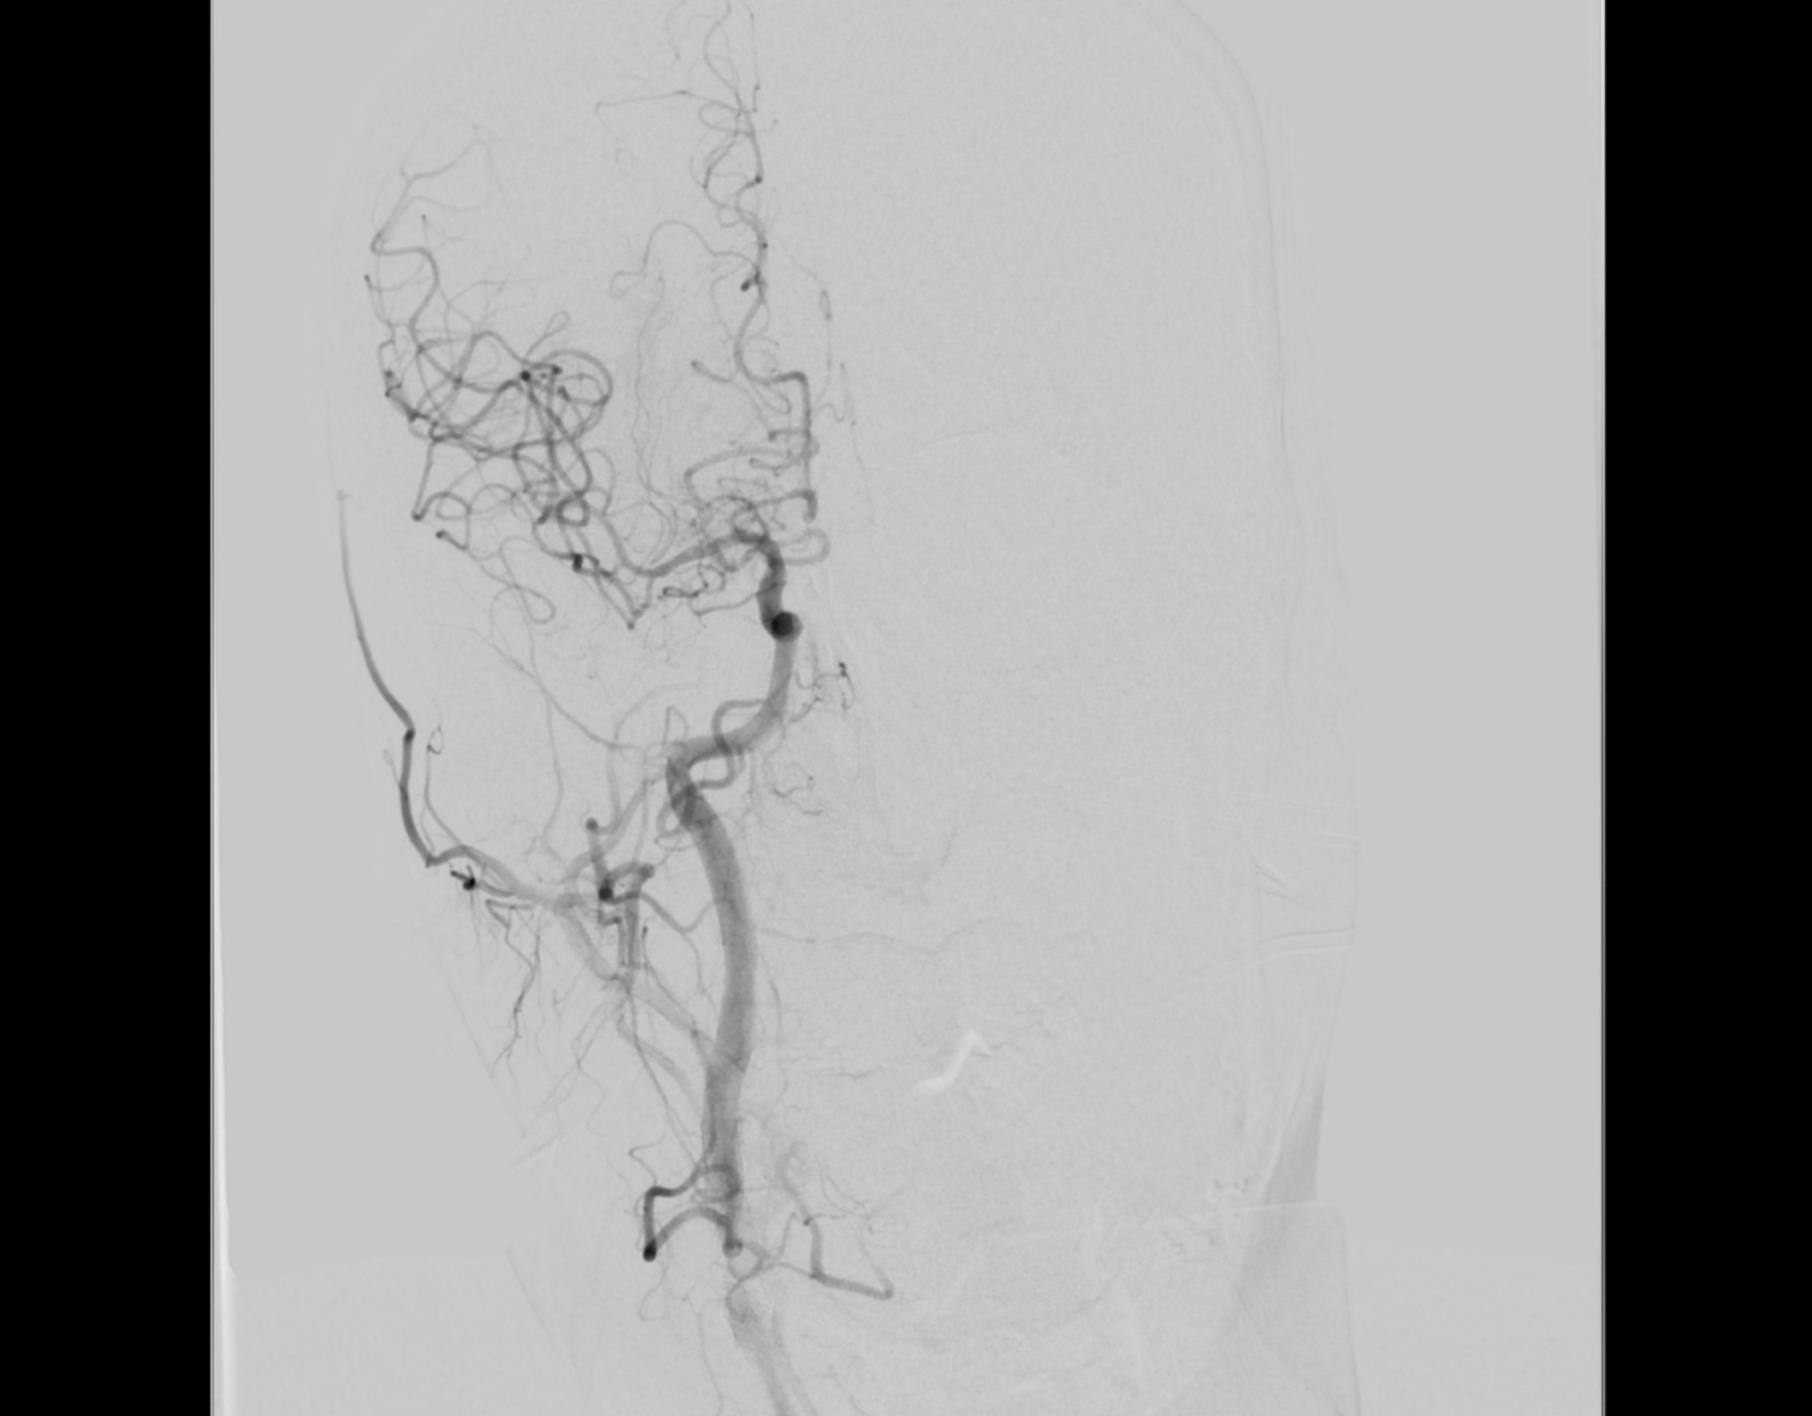

CTA提示右侧颈内动脉及大脑中动脉闭塞

右侧颈内动脉及大脑中动脉恢复通畅